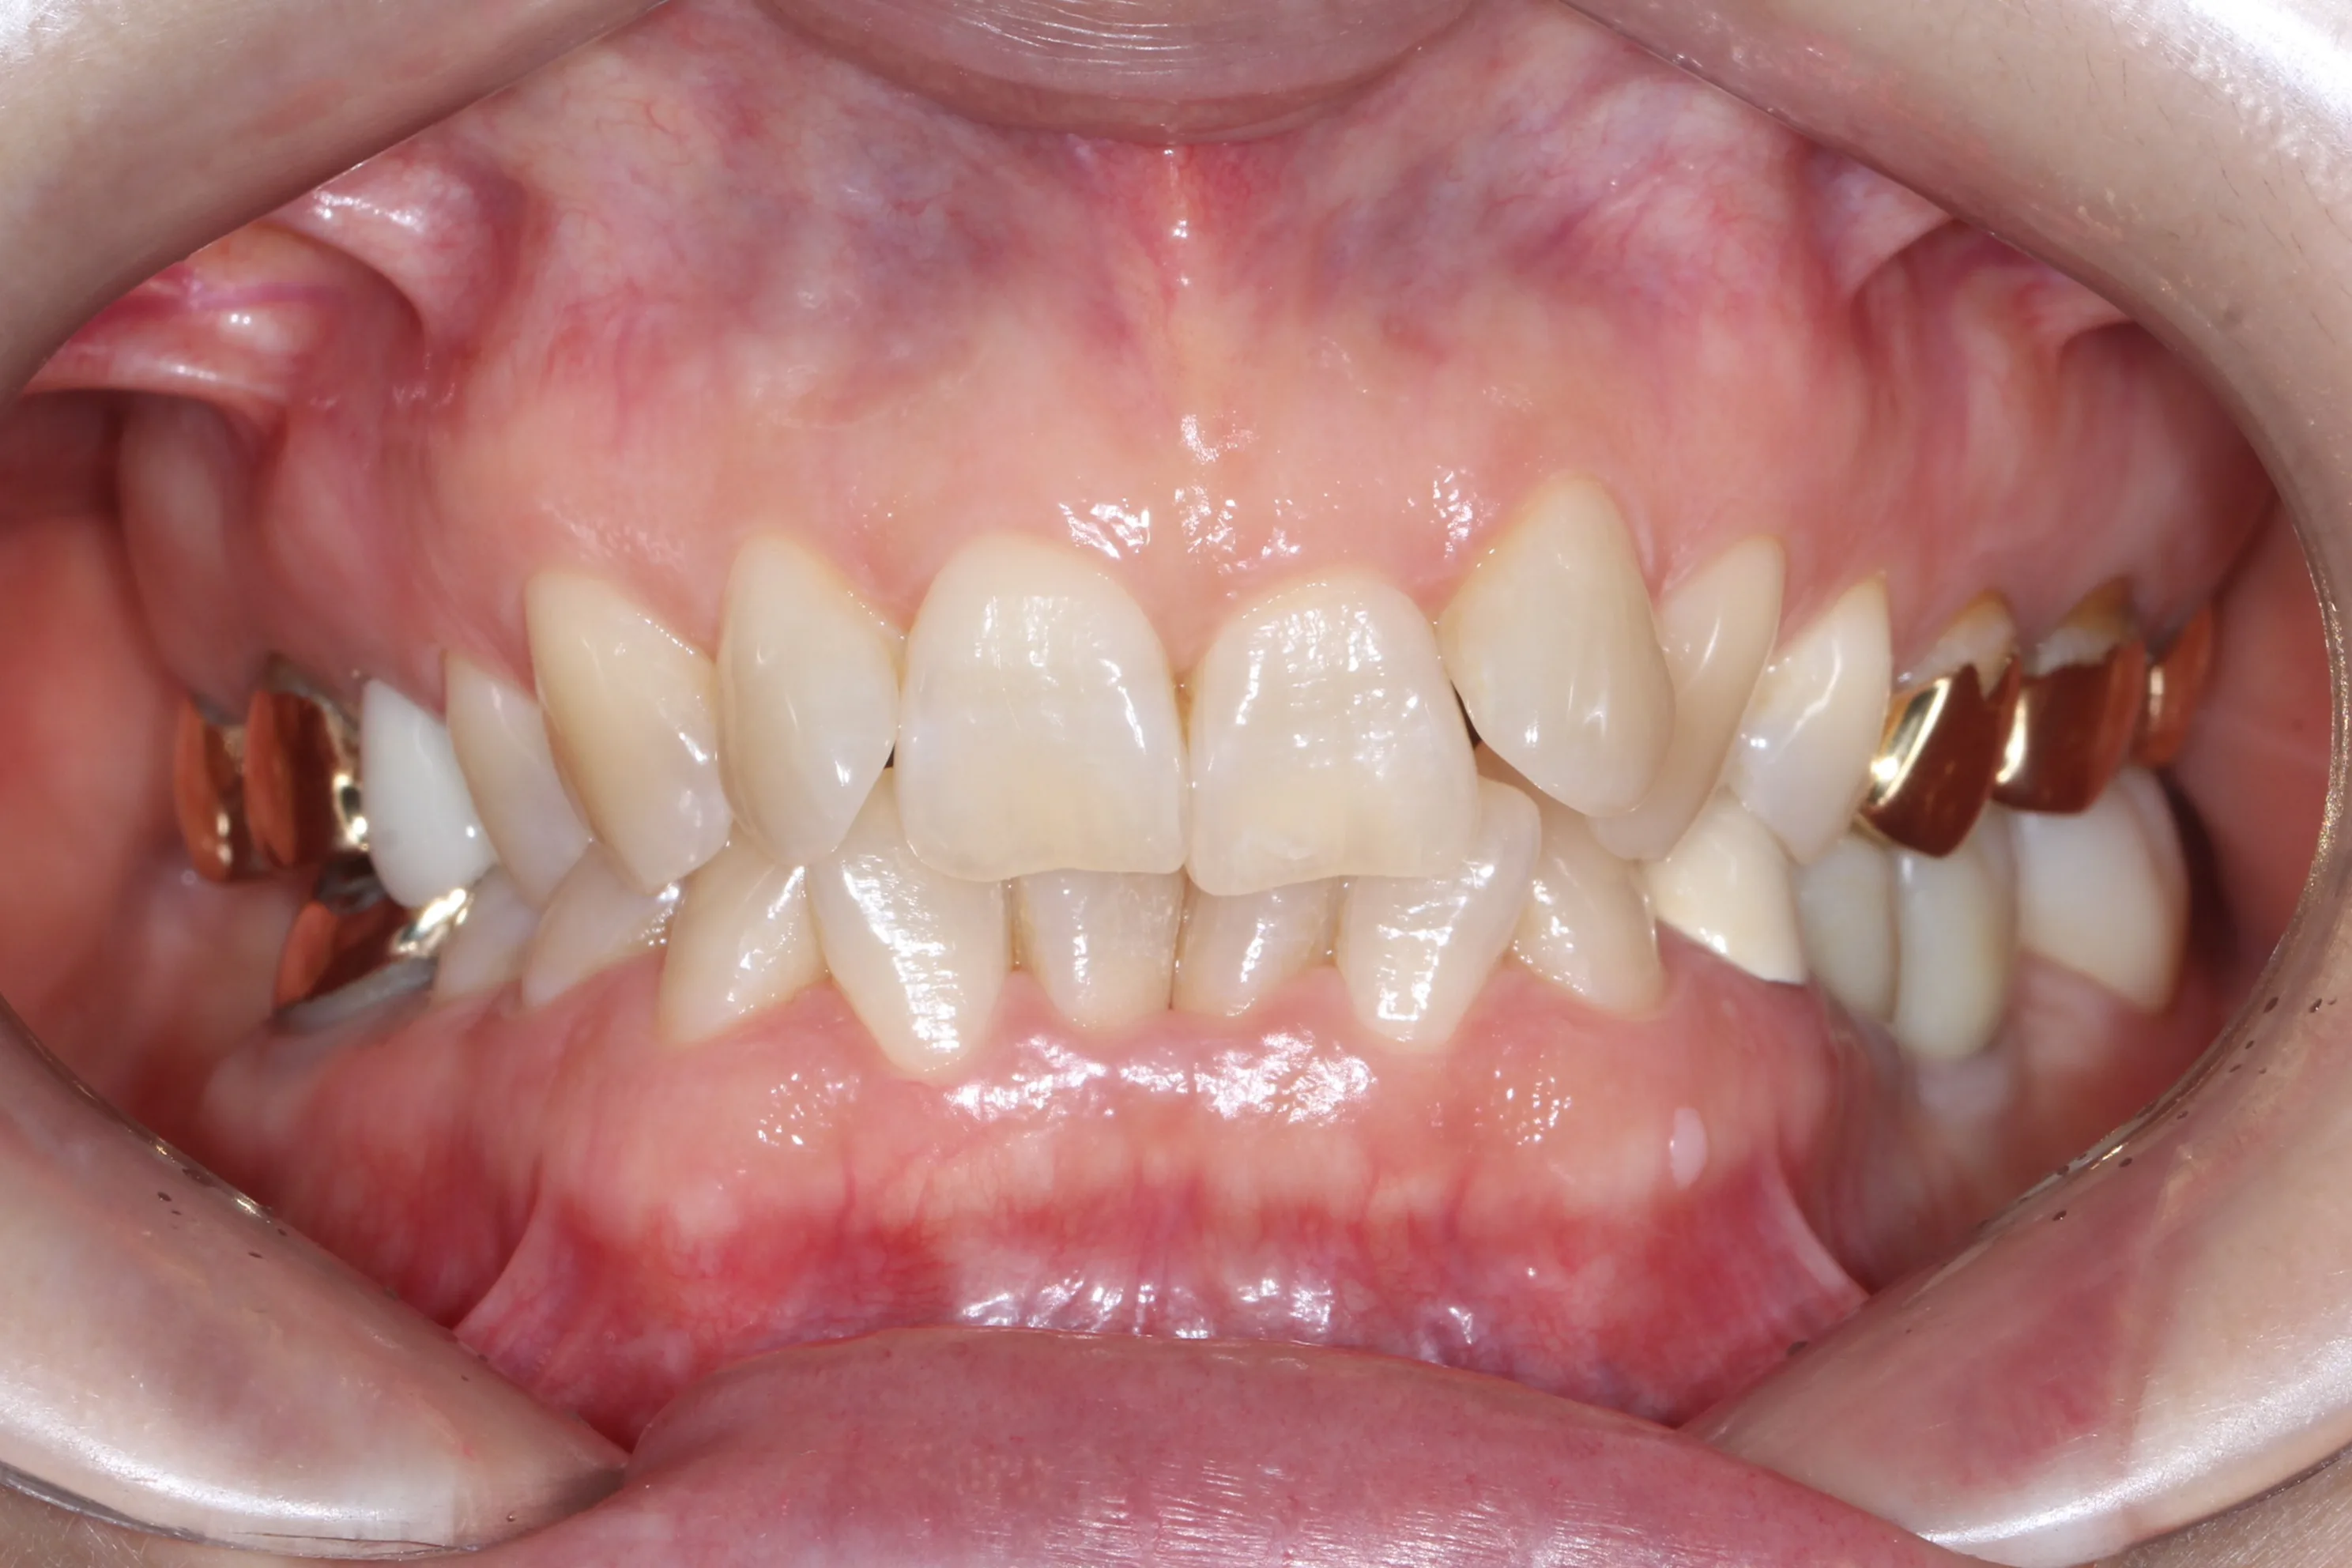

이 환자분은 이미 구강 안에 여러 개의 임플란트와 브릿지 보철물이 있는 상태였습니다. 앞니는 가지런하지 않고, 윗니가 아랫니를 깊게 덮는 과개교합(deepbite)도 있었습니다. 이런 경우 가장 중요한 것은 기존 임플란트와 보철물의 교합을 그대로 유지하면서, 나머지 치아만 가지런하게 배열하는 것입니다.

인비절라인의 디지털 치료 계획을 활용해서, 임플란트와 보철물이 있는 어금니는 움직이지 않도록 고정하고 앞니 위주로만 이동시켰습니다. 덕분에 발치 없이, 고무줄이나 미니스크류 같은 추가 장치 없이도 15개월 만에 치료를 마무리할 수 있었습니다.